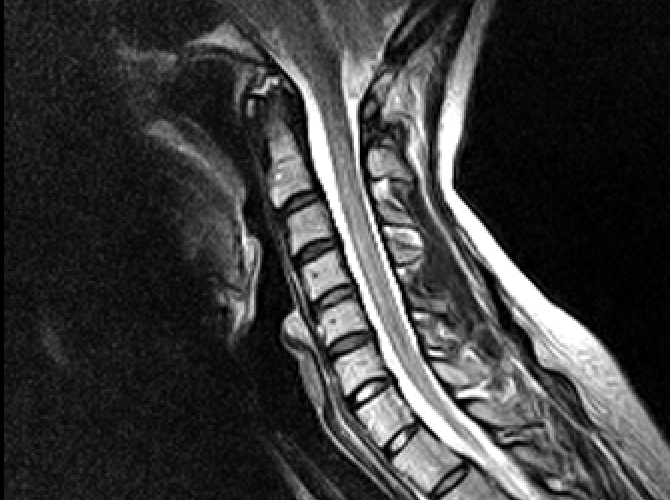

I had no direction from Dr’s. Through hours of research I would find new disorders that would be comorbid to my condition and research those. Each one adding a piece to the puzzle. I’d find out what scans I’d need, blood work, where to go. Call around till I found the place and then contact my family Dr. I’d bring him up to speed on where I was at in my research and he would write the order I needed to travel out of state to get my MRI’s, and CINE scan.

I have to say the hospital is quite efficient here. In a matter of a hour I had 5 X-rays, blood, urine, covid, and cat scan done. We then went to a different clinic where we did a MRV scan. It is a 3D mapping of my arteries, and veins. We did see how things had moved with my instability. We gained valuable information through this scan. Turns out my right jugular doesn’t have blood flow basically at all. We hope that the fusion will be enough to unpinch this so I can avoid a jugular decompression.